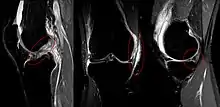

La tríada de O'Donoghue, también llamada tríada desgraciada o tríada infeliz, es una lesión compleja de rodilla en la que existen tres lesiones diferentes de forma simultánea: rotura del ligamento cruzado anterior, rotura del ligamento lateral interno y rotura del menisco interno. Se provoca como consecuencia de traumatismos sobre la rodilla, predominando en varones jóvenes y con mucha frecuencia en relación con la práctica deportiva, sobre todo del fútbol. El diagnóstico se basa en la sintomatología y se confirma mediante la realización de radiografía, resonancia magnética nuclear y artroscopia. El tratamiento es siempre quirúrgico seguido de un periodo de rehabilitación y fisioterapia.[1]